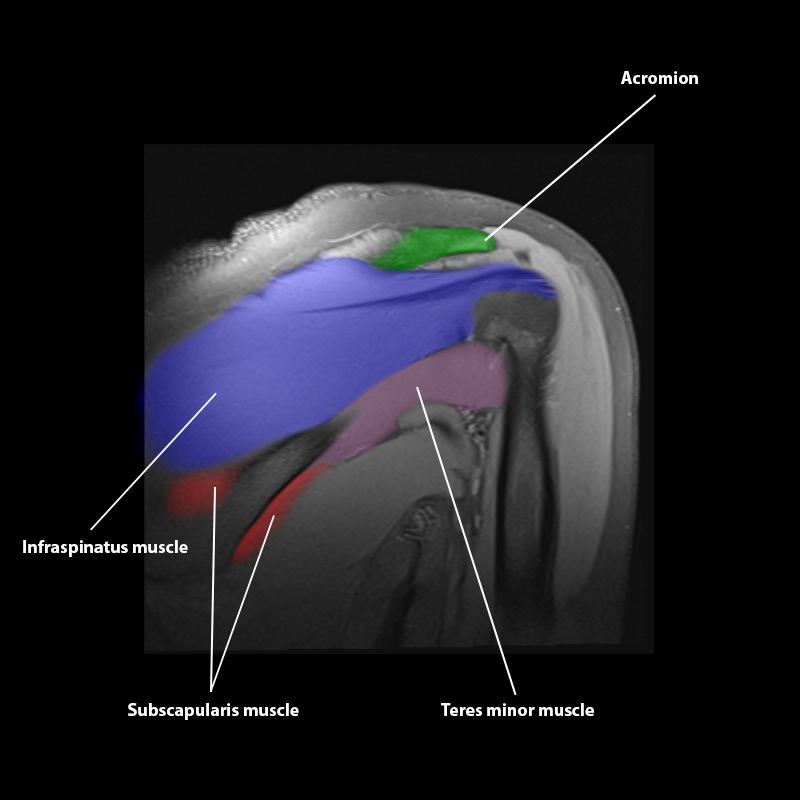

Shoulder MRI Anatomy